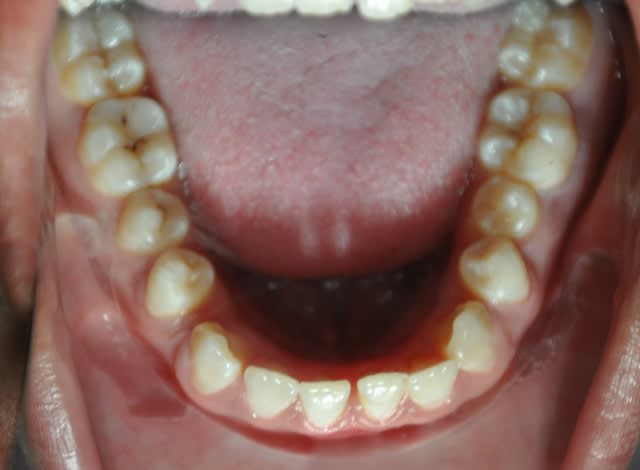

cas clinique:articulé débordant d'un seul coté

comment on peut traiter cet articulé gauche

Concernant l’occlusion croisée à gauche, il y a deux problèmes : un problème vertical d’égression à partir des canines et un problème transversal.

les dernieres photos du cas